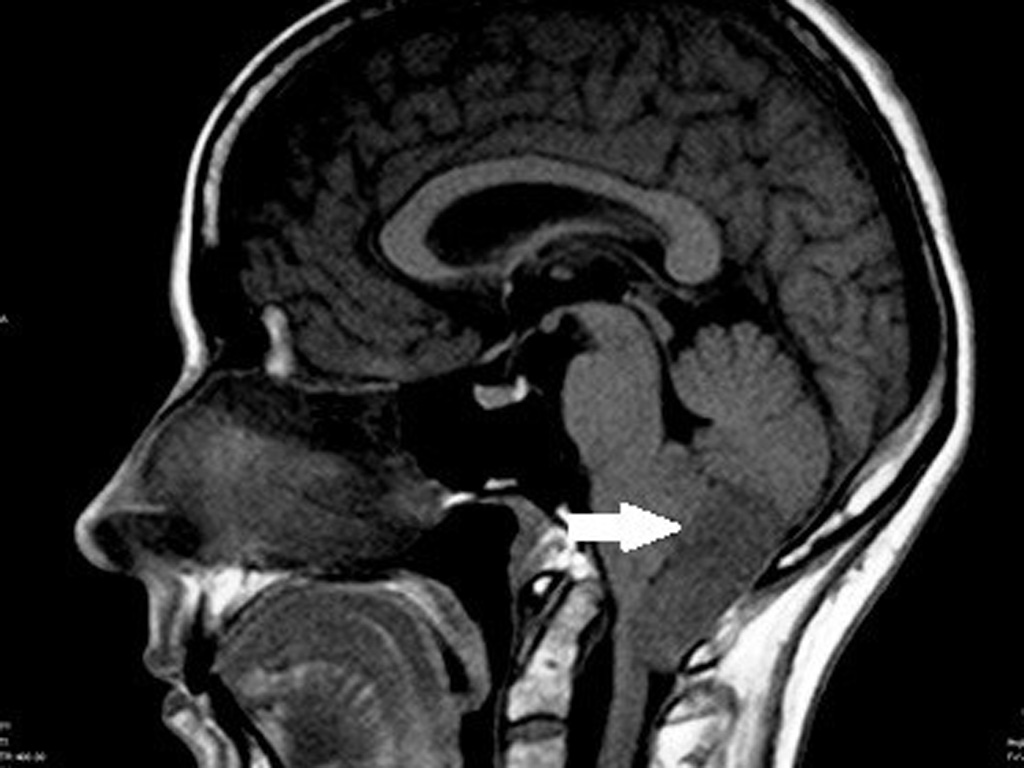

- Магнитно-резонансная томография (МРТ), при которой для создания изображения головного мозга, используются радиоволны и магнитные поля, что помогает выявить опухоль на ранней стадии заболевания, определить расположение опухоли и назначить план лечения;

После полной диагностики врач формирует индивидуальный план лечения, принимая во внимание размер и локализацию опухоли.